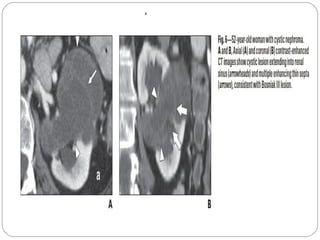

MULTILOCULAR CYSTIC NEPHROMA

Tumor of primitive renal tissue

originating from metanephric

blastaema

Pathology – cyst with septa that

contain renal tissue of variable

maturity

Bimodal age distribution.

 Under the age of 5 years, cystic

nephroma occurs most frequently in

males, whereas the adult group has a

female predominance (91%) and

mean age of 55 years

Septate cystic mass with

multiple loculations,

hairlike septa,peripheral

and curvilinear

calcifications,irregular

borders, and minimal

contrast enhancement.

Extension into the

central sinus and into the

renal pelvis can also be

found

IVU – Multiple non enhancing areas bulging into renal pelvis

USG/CT/MRI –

Well defined multiloculated mass with an apparent capsule

Little or no enhancement

Calcification is usually not a feature